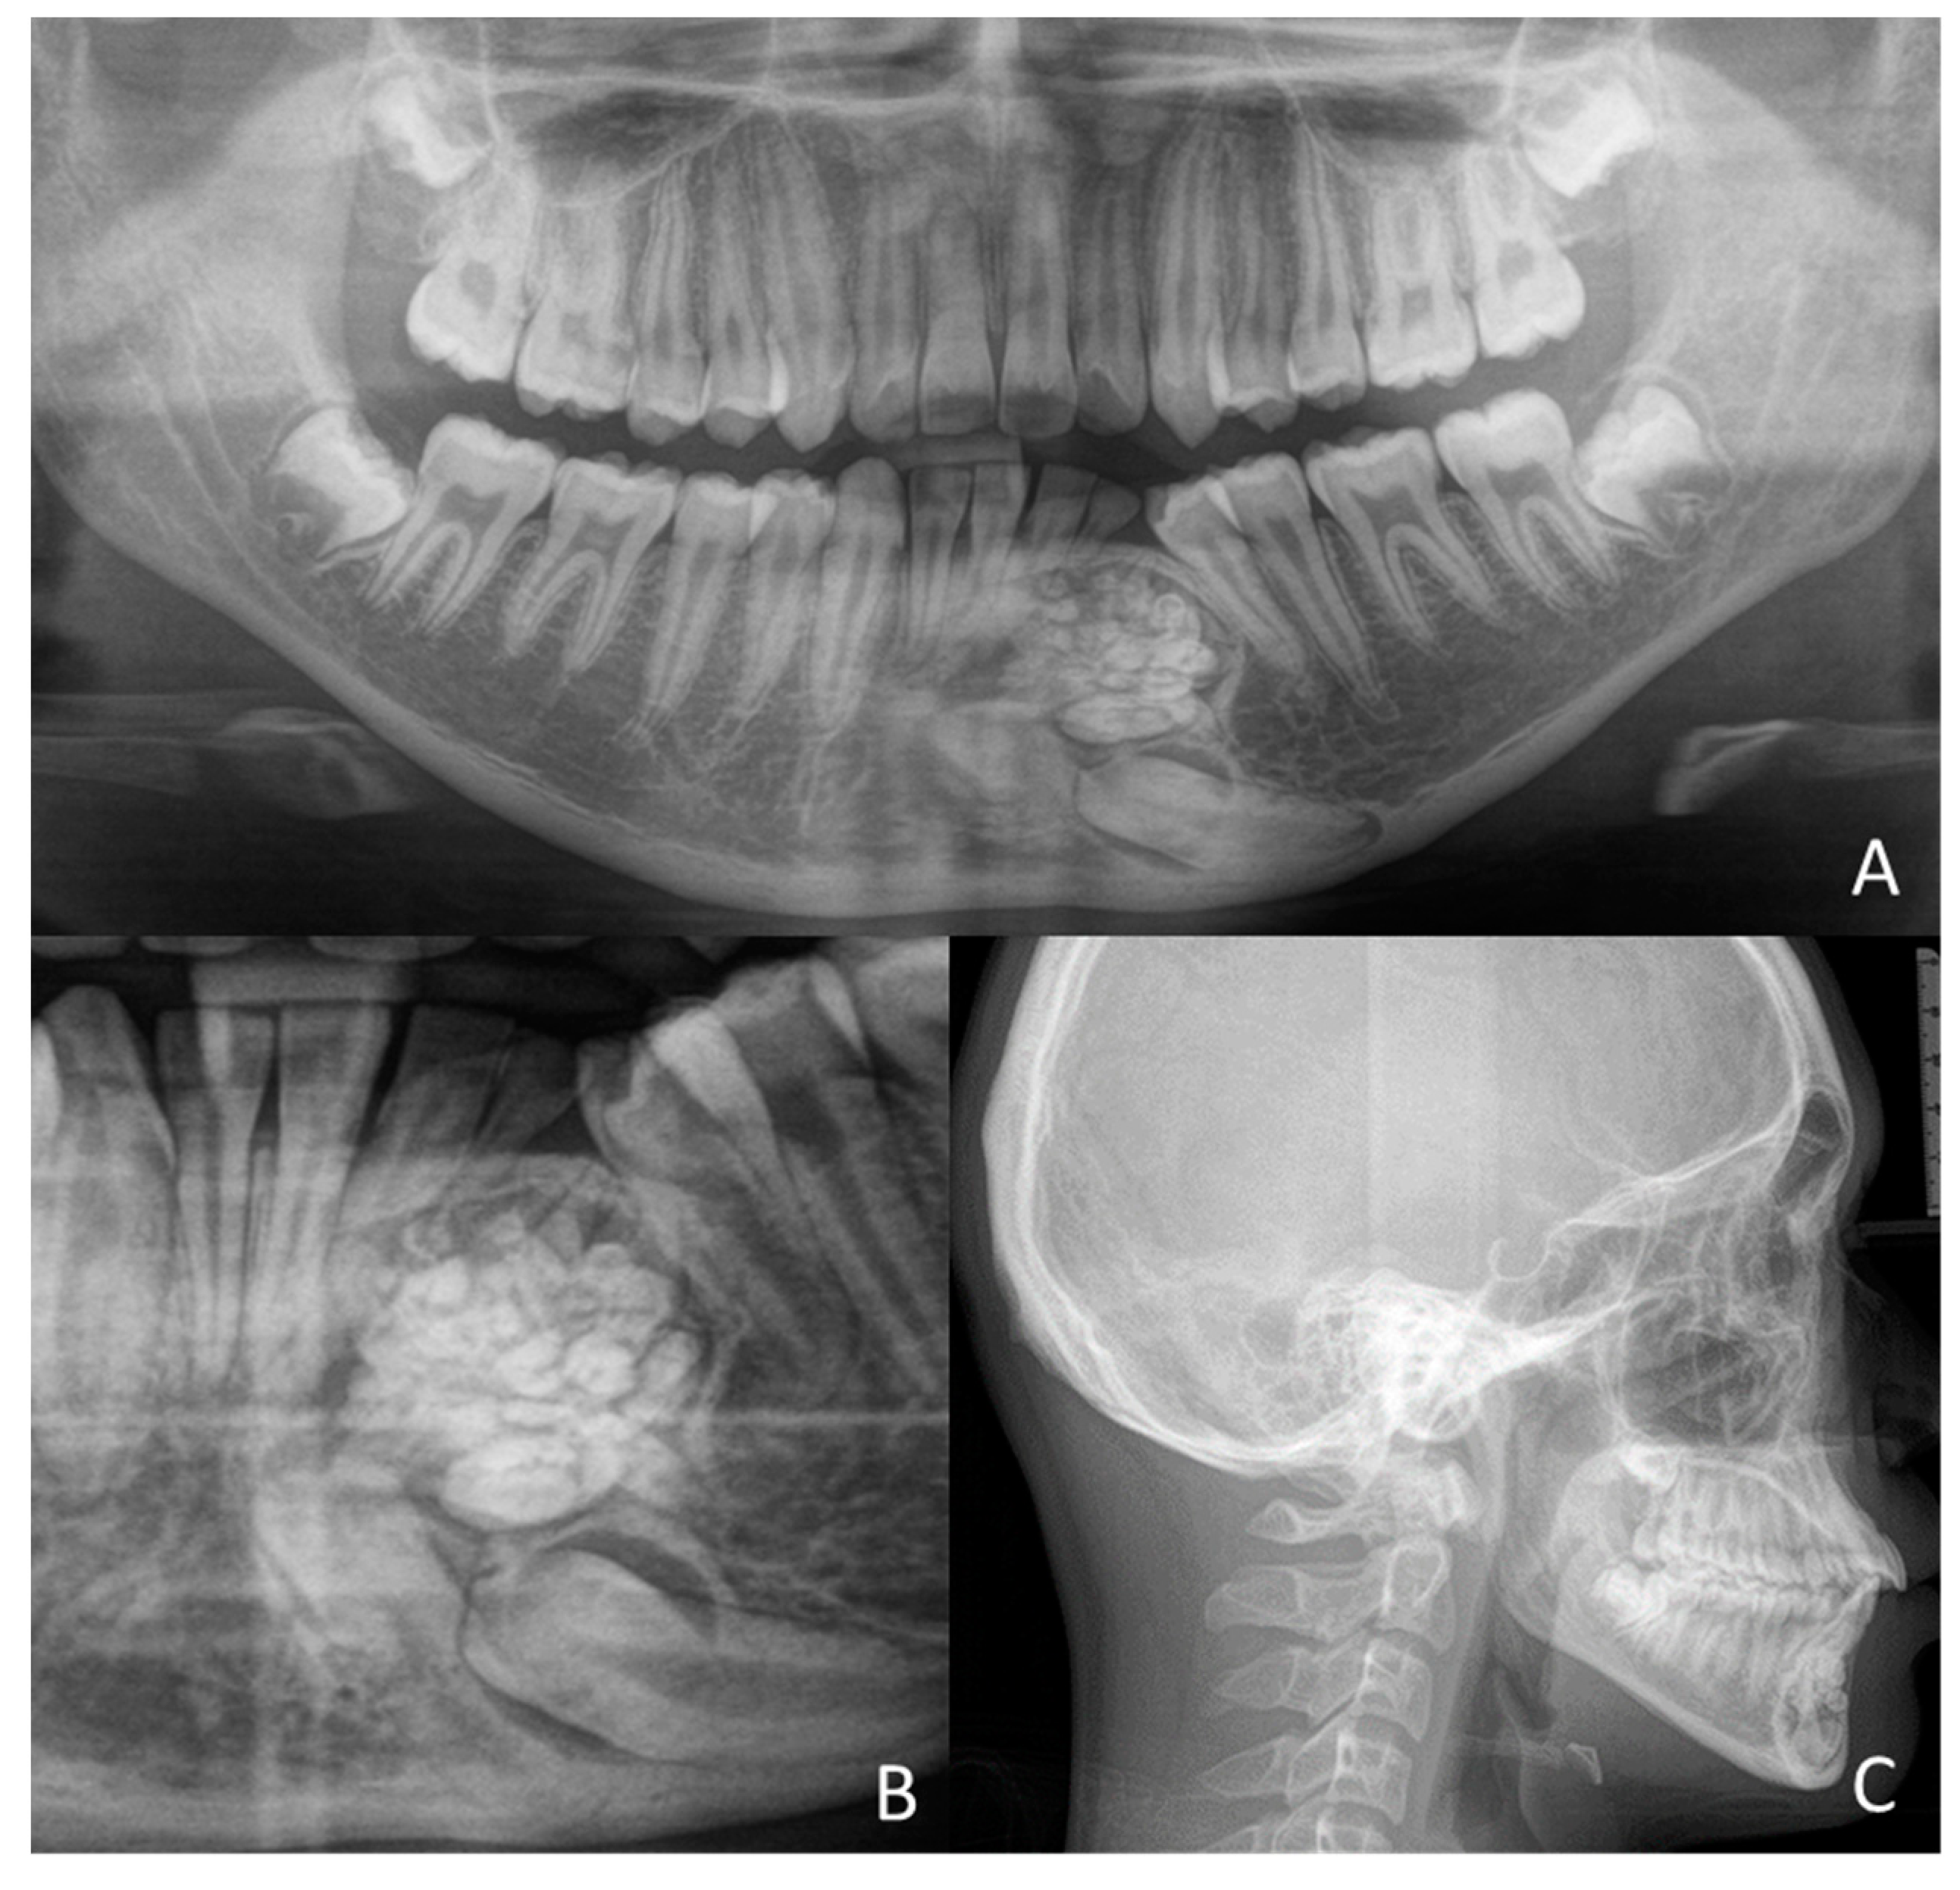

1.1. Case Number 1

1.2. Case Number 2

1.3. Case Number 3